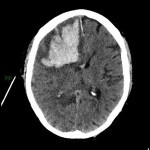

COVID-19-Impfung: Gehirnblutung mit Ventrikelriss: Noch einer dieser Einzelfälle nach Gentherapie mit Pfizers Comirnaty

Die Frage, wann die Nebenwirkungen nach Impfung so zahlreich sind, dass man sie a) nicht mehr unter den Teppich kehren und b) als Einzelfall abtun kann, wie das derzeit getan wird, in einem Experiment in Kollektivismus, das man auf die Formel bringen […]